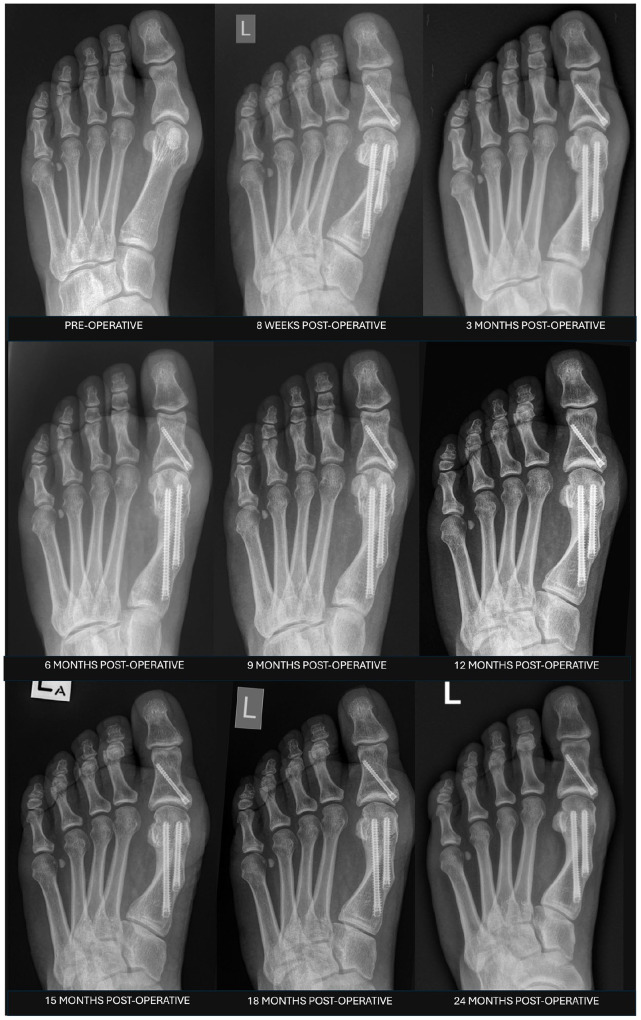

Background: Minimally invasive or percutaneous surgery (MIS) for hallux valgus correction has seen increased adoption because of a growing evidence base of positive clinical and radiographic outcomes following surgery. However, no standardized or validated radiographic classification exists to evaluate the first metatarsal osteotomy healing following MIS hallux valgus surgery. The aim was to develop a new radiographic classification system for assessing bone healing following MIS distal transverse osteotomy for hallux valgus.

Methods: A 4-domain radiographic classification system based on callus formation, anteroposterior (AP) osteotomy line, lateral osteotomy line, and remodeling for MIS osteotomy healing was developed and tested on a cohort of 27 feet that underwent percutaneous transverse osteotomy for hallux valgus correction. Patients had simultaneous postoperative weightbearing computed tomography (WBCT) and standard radiographs following surgery. Five surgeons reviewed anonymized radiographs to evaluate interobserver reliability. WBCT was used to confirm union status and classification interpretation.